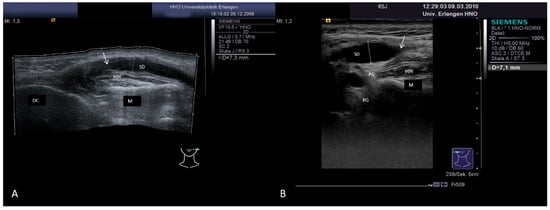

3.3.2. Obstructive Sialadenitis Caused by Sialolithiasis